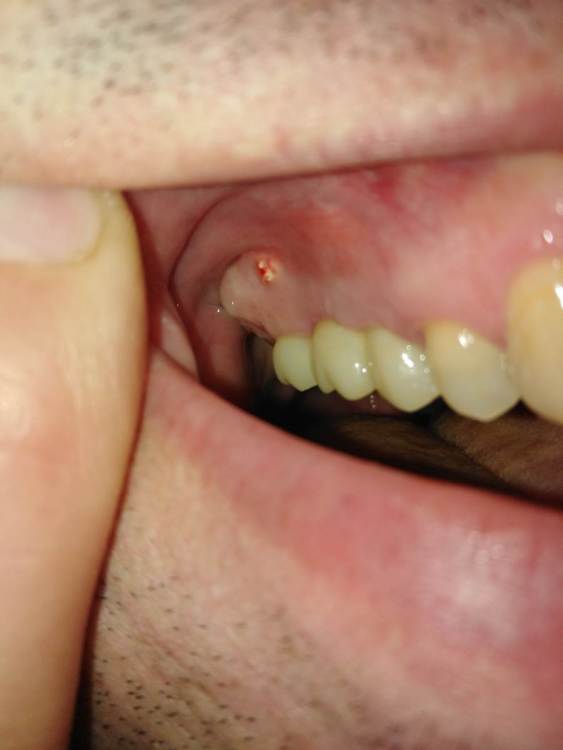

еатегsffhgj Опубликовано 5 сентября, 2021 Автор Поделиться Опубликовано 5 сентября, 2021 белая штука на десне превратилась вот во что. и,что делать? она на болит,но как будто порвала десну и вылезла наружу Ссылка на комментарий

еатегsffhgj Опубликовано 6 сентября, 2021 Автор Поделиться Опубликовано 6 сентября, 2021 (изменено) сходил к врачу. он вытащил несколько крошек. говорит,или крошка,которая снаружи добавлялась не прижилась,или из пазухи выдавливает. кт он не видел. только панораму. крошки вытащил,но дальше не смог расковырять. кость твердая,вроде. надо ему принести кт? как вы думаете,какой вариант наиболее вероятен?. сказал показаться в конце недели. Изменено 6 сентября, 2021 пользователем еатегsffhgj Ссылка на комментарий

Irouil Опубликовано 6 сентября, 2021 Поделиться Опубликовано 6 сентября, 2021 На мой взгляд никакого практического значения в том, из какого конкретно аугментата эта крошка прорезалась, нет. Если в конце недели все равно планируется осмотр, то мне кажется логично показать доктору КТ 1 Ссылка на комментарий

Irouil Опубликовано 7 сентября, 2021 Поделиться Опубликовано 7 сентября, 2021 Вероятность несостоятельности имплантата в Вашей ситуации исчезающе мала прорезавшаяся крошка - это часть «порошка», которым заполняли костные дефекты. Процесс этот, обычно, очень компактный, в дефекты его достаточно надежно «трамбуют». Но одна-другая крупинка могут сбежать в толщу раны и тогда, рано или поздно, они вылезут на поверхность, чем их приключения и закончатся - как произошло в Вашем случае. А из какого именно дефекта данный беглец улизнул я значимой разницы не вижу 1 1 Ссылка на комментарий